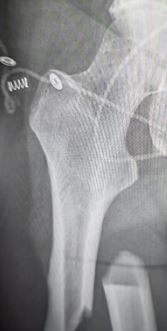

Broken thigh bone due to bone loss from osteoporosis in 40s